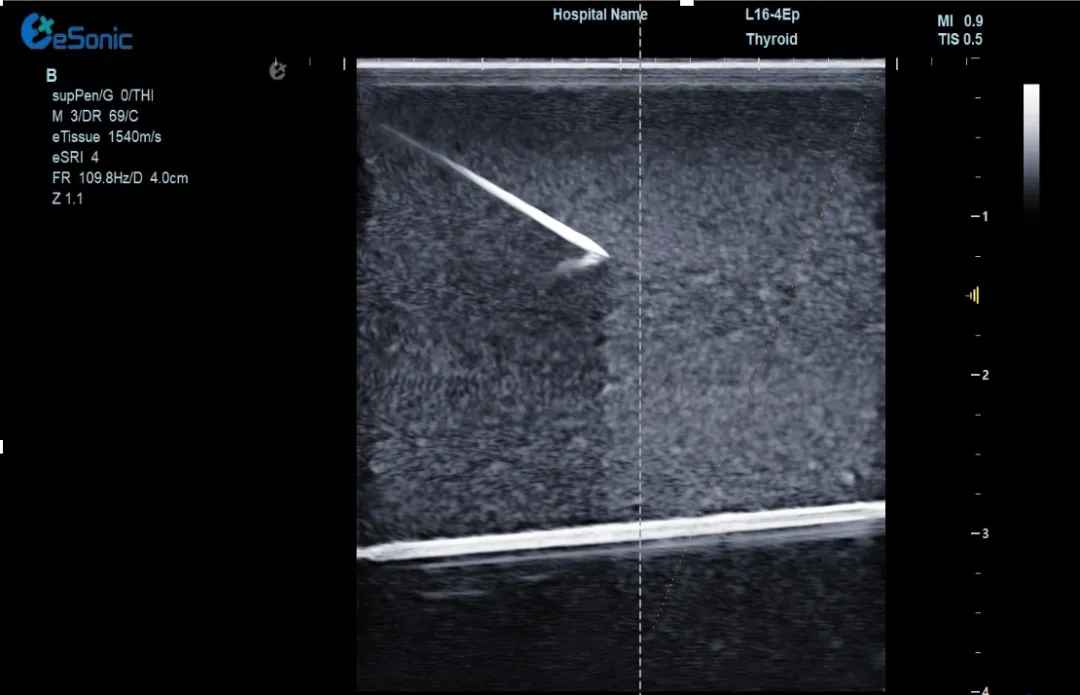

(1)实时追踪针尖:超声增强技术全程显示针尖位置,避免误伤血管、神经,穿刺成功率提升50%!

穿1.jpg

(2)动态路径预判:AI算法提前规划最佳穿刺路径,复杂位置的肝肿瘤、甲乳结节也能“一针到位”。可广泛应用于椎管穿刺或消融治疗等,使医生更易区分针尖和韧带等强回声,实时定位针尖位置,减低有创操作风险。